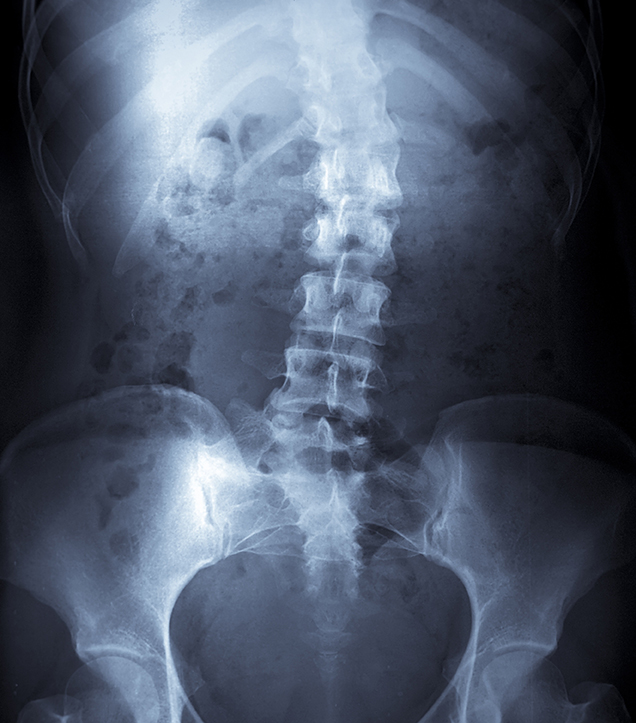

Accurate, safe, and immediate diagnosis with on-site digital X-rays.